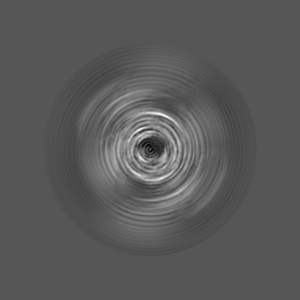

In vitro assembled 266/297 - 391 tau filaments with MgCl2 and NaCl (14b)

EMD-14044

Helical reconstruction

3.26 Å

Sample Organism: Homo sapiens

Sample: Tau

Fitted models: 7qkj

Deposition Authors: Lovestam S, Scheres SHW

Assembly of recombinant tau into filaments identical to those of Alzheimer's disease and chronic traumatic encephalopathy.

Lovestam S, Koh FA, van Knippenberg B , Kotecha A , Murzin AG, Goedert M , Scheres SHW

(2022) eLife , 11

PUBMED: 35244536

DOI: doi:10.7554/eLife.76494